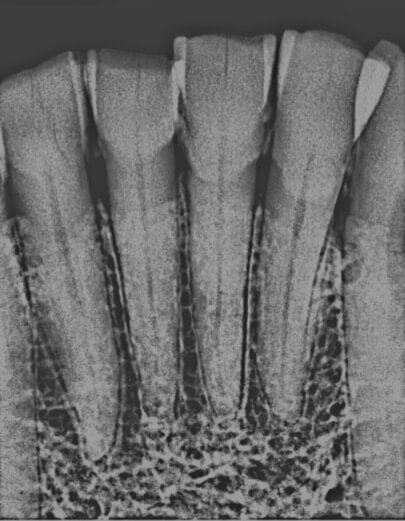

Using an X-ray is part of the research technique.

Examining pulp chambers -- which fill in as people get older -- is promising for better determining an age on a skeleton because that area of the tooth is more protected than enamel, Madden said. With enamel studies, researchers could only determine an age range for skulls up to about middle age; with pulp chamber studies, they are able to pinpoint age groups in a range up to the 60s with a diminished error rate.

Madden and Piechocki X-rayed the teeth, used pixels to measure the filling in the pulp chamber and then used an equation to produce their findings.